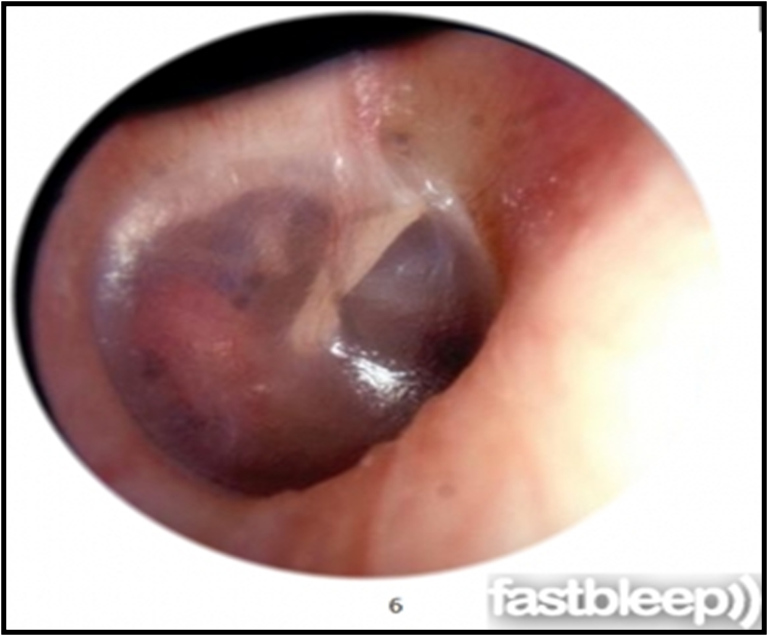

- OE: Schwartze sign